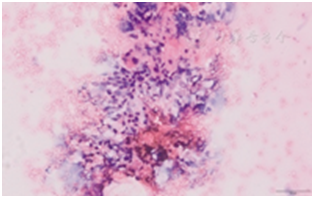

遇标本内血液成分较多时(图26),可以采取以下措施减轻红细胞对镜下观察标本效果的干扰。①将标本分散至数张载玻片,避免单张涂片标本过厚,削弱红细胞对其它细胞的覆盖程度。②穿刺操作时,根据具体情况在抽吸法和非抽吸法之间灵活转换应用。抽吸法穿刺获得标本含血液较多时,可以改为非抽吸法再次穿刺;非抽吸法穿刺获得标本含量较少时,可以改为抽吸法再次穿刺。③采用TCT细胞采集技术,消除红细胞的影响,提高甲状腺结节细胞的观察效果。

图26标本中血液成分过多 A:肉眼观标本量充足,但是以血液为主;B:光镜下见红细胞过多(×10)

当不具备现场快速细胞学评估条件时,通过培训非细胞学医生对置于载玻片上的标本或液基保存液中的标本进行现场裸眼评估的技能,具有较高的可行性和一定的实际效果。现场观察发现标本稠厚,意味着标本中细胞数量更多、更充分,显微镜下的细胞学诊断效能更高(图27)。反之,标本稀薄则提示细胞量可能不足,影响细胞学诊断效能(图28)。标本中颗粒物丰富者,意味着镜下细胞量较多,易获得有效诊断,得到阳性结果的比例也更高(图29);颗粒物较少甚或无颗粒物者则反之。尽管现场裸眼评估不能代替镜下分析,但通过评估可合理调整穿刺针数,增强操作者穿刺成功的信心[31]。

图27标本稠厚,且颗粒物丰富 A:肉眼观标本量充足,肿瘤组织颗粒较多,血液成分较少;B:光镜下见肿瘤细胞多,红细胞较少(×10)

图28标本稀薄,血液成分少且颗粒物亦较少 A:肉眼观标本量不足,质地稀薄;B:光镜下见标本稀薄,细胞少(×10)

图29标本量充足,肿瘤组织颗粒丰富 A:肉眼观颗粒物丰富,血液成分较少;B:光镜下观乳头状癌肿瘤细胞的细胞核明显(×10)